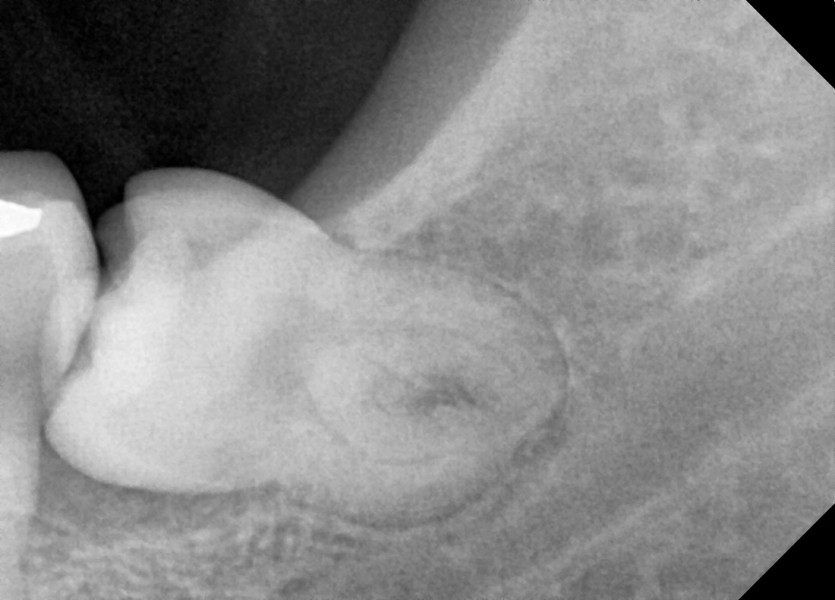

#38,48 사랑니 발치

구강 외과 전문의가 당일 발치했습니다.